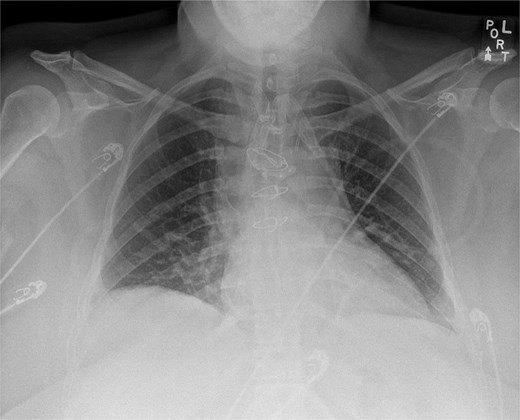

Postoperative chest X-ray demonstrating sternal wire and sternal plate closure.